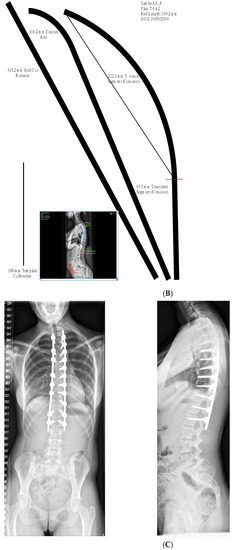

2. Materials and Methods

3.3. Comparison of TK Achieved with Templating

- Restoring TK to a value of 20–40° regardless of pre-operative TK value.

- Post-operative TK achieved was within 5.5° of the value predicted using templating.